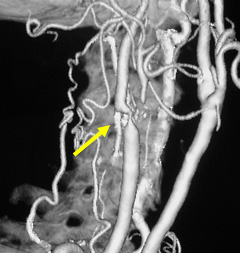

写真左:頚動脈狭窄所見

写真右:ステントを用いて狭窄部を拡張し治療